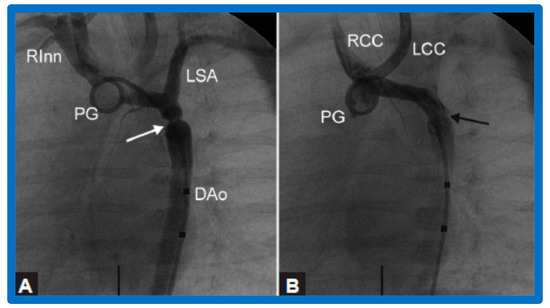

3.3. Aortic Coarctation, Native

4.3. Aortic Coarctation–Native